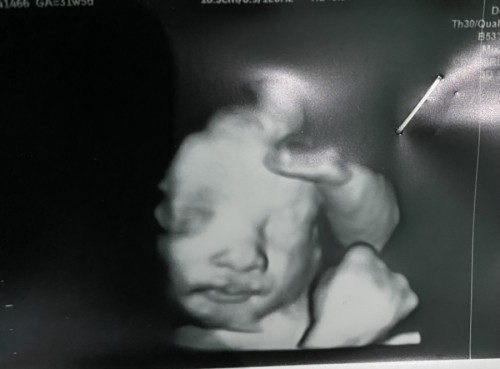

ภาพอัลตราซาวด์น้อง31 6 W

สอบถามแม่ๆๆหน่อยค่ะตอนนี้น้อง31 6Wแล้วภาพอัลตร้าซาวด์ช่วงปากน้องแปลกๆๆน้องจะผิดปกติมั้ยคะ

ถ้าคุณหมอไม่ได้บอกอะไร น่าจะปกตินะคะ